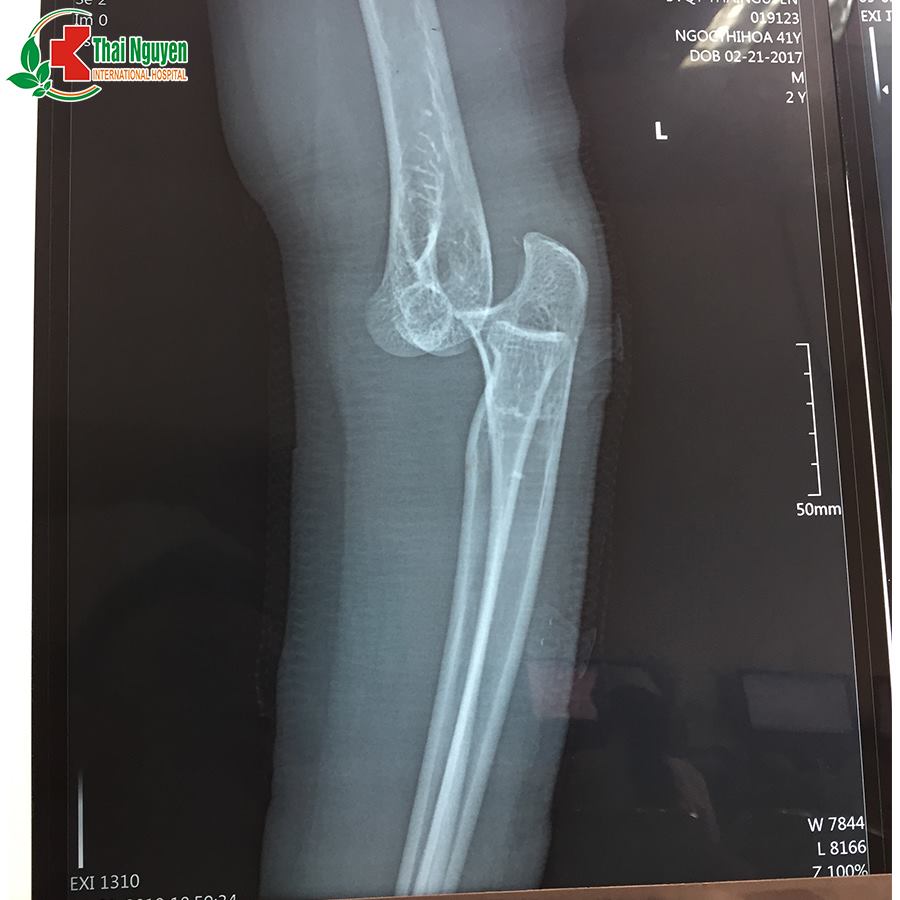

Ngày 01/03/2019, bệnh nhân Ngọc Thị Hoa, 41 tuổi, khuỷu tay trái bị sưng nề, khó cử động, sau khi đắp thuốc nam 1 tháng không có hiệu quả, bệnh nhân đã đến BVQT Thái Nguyên khám và điều trị. Sau khi thăm khám, chụp X-quang đã phát hiện bị trật khớp khuỷu tay trái.?? BSCK2 Lê Văn Bằng đã chỉ định phẫu thuật đặt lại khớp cho bệnh nhân do trật khớp đã lâu có biến chứng. Ca phẫu thuật thành công và hiện tại bệnh nhân đang trong quá trình hồi phục.

??Trật khớp khuỷu thường do chấn thương; ngã ở tư thế chống tay, khuỷu tay duỗi, cẳng tay ngửa. Tổn thương có thể đứt các dây chằng, rách bao khớp, có thể vỡ đầu dưới xương cánh tay, vỡ mỏm khuỷu.